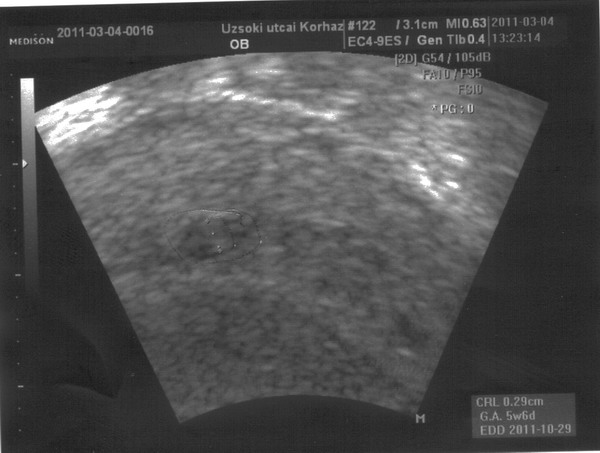

Képzeljétek! Nálunk az lett a helyzet, hogy a tegnapra nem-megtermékenyült drágaságunk délutánra megtermékenyült és ma 6sejtesként visszakaptam, illetve a 4 tegnap megszúrtból is egy lett szép, mire visszakaptam el is kezdett osztódni, így kétsejteske lett!!! Annyira boldogok vagyunk! Nem kaptam ovitrelle-t, mert 22 mm folyadék van a pociban... sebaj, nagyobb valószínűséggel maradnak meg a bébikéink....

Lányok mellékelek két képet, ők DÉVAI-s babák, a barinőm kisfia és kislánya, már régen szeretne jönni hozzátok, és megírni, hogy mindenkinek fel a fejjel, mert Dévai mindenkinek "csinál" kisbabát. Ők is rá az élő példa, de egyelőre a két gyerkőc annyira leköti minden idejét, hogy engem kért meg, hogy tegyek fel két képet, ami adjon mindenkinek erőt, hitet ebben az egészben, mert SIKERÜLNI FOG!!!! Ha tud jön majd és ír is nektek!

Hát nem gyönyörűek????